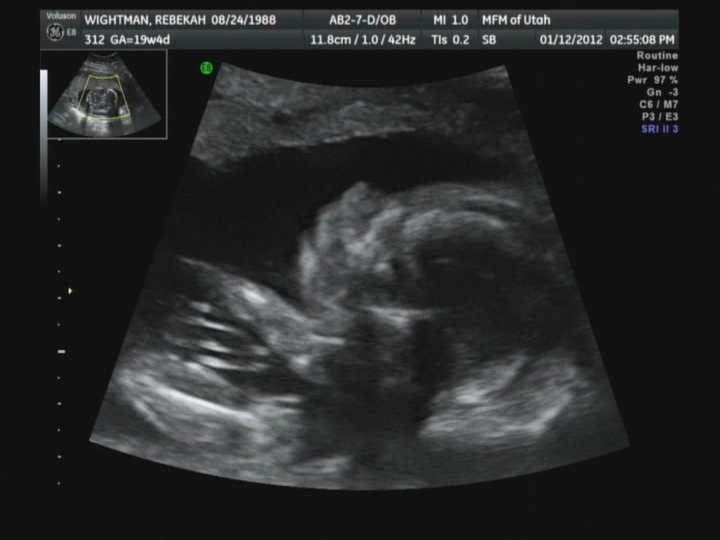

Yesterday, at the appointment, this little fellow was not very eager to display his goods. It took a lot of coaxing to get him to split his legs. The ultrasound tech kept pushing on my stomach and he would move his arms and push back like, "lay off lady, I'm trying to sleep!" After a few of those punches, he finally just took both arms and covered his face so just his sweet little nose poked out between them.

My favorite comment that the ultrasound tech made during the visit went as follows, "The brain looks good, the heart is beautiful, all the organs look good.....WOW, those are really long femur bones. He's got some seriously long legs." Indeed, the babe will be quite long/tall.